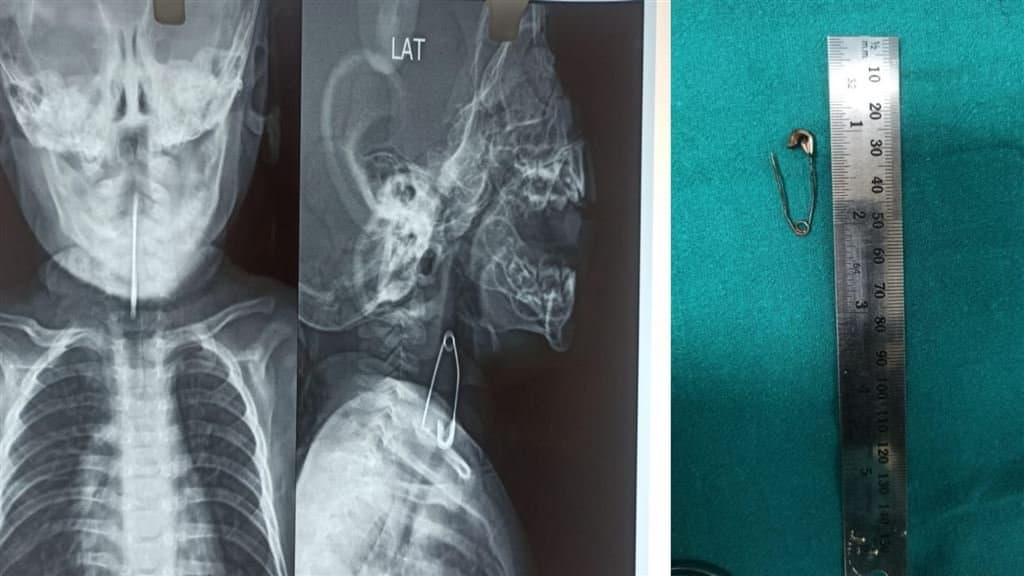

বিভাস ভট্টাচার্য: খাটে শুইয়ে ছিল পাঁচ মাসের ছোট্ট ভাই। পাশেই অন্য ভাইবোনরা তাকে নিয়ে খেলছিল। খেলতে খেলতেই কোনওভাবে ভাইয়ের মুখে ঢুকে যায় মুখ খোলা প্রায় এক ইঞ্চি লম্বা একটি সেফটিপিন। ভাই সেটা গিলে ফেলে। সেফটিপিন আটকে যায় শ্বাসনালীর ঠিক আগে। শুক্রবার কলকাতা মেডিক্যাল কলেজে ইএনটি বিভাগের চিকিৎসকরা অস্ত্রোপচার করে সেফটিপিনটি বের করে শিশুটিকে বিপন্মুক্ত করেন। কিন্তু পাঁচদিন আগে এই ঘটনা ঘটলেও হুগলির জাঙ্গিপাড়ার বাসিন্দা ওই শিশুটির বাবা-মা বিষয়টি প্রথমে একেবারেই বুঝতে পারেননি। বাচ্চাটির মুখ থেকে অবিরত লালা ঝরছিল এবং সেইসঙ্গে কিছু খেতেও চাইছিল না। স্থানীয় এক চিকিৎসককের কাছেও নিয়ে যাওয়া হলে তিনি শিশুটির ঠান্ডা লেগেছে বলে সেই অনুযায়ী ওষুধ দেন। কিছুতেই অবস্থার উন্নতি না হওয়ায় বৃহস্পতিবার বিকেলে শিশুটির অভিভাবক তাকে নিয়ে কলকাতা মেডিক্যাল কলেজে এলে এমার্জেন্সি বিভাগ থেকে শিশুটিকে ইএনটি বিভাগে পাঠিয়ে দেওয়া হয়।প্রাথমিক পরীক্ষায় সন্দেহ হলে গলায় এক্সরে করিয়ে দেখা যায় সেফটিপিনটি ঠিক শ্বাসনালীর মুখে আটকে আছে। এবিষয়ে হাসপাতালের ইএনটি চিকিৎসক ডা. সুদীপ দাশ বলেন, 'শরীরের ভেতরে সেফটিপিন মুখ খোলা অবস্থায় ঢুকলে একরকমের বিপদ আর মুখ না খোলা অবস্থায় ঢুকলে আরেকরকম বিপদ। এটা বলার অপেক্ষা থাকে না মুখ খোলা সেফটিপিন অনেকবেশি বিপজ্জনক। কিন্তু এই শিশুটির ক্ষেত্রে সেরকম কিছু হয়নি কারণ সেফটিপিন শ্বাসনালীর ভেতরে প্রবেশ করেনি।' শুক্রবার ৪০ মিনিটের অস্ত্রোপচারে সেফটিপিন বের করে আনা হয়। অস্ত্রোপচারে ডা. সুদীপ দাশ ছাড়াও ছিলেন ইএনটির অপর দুই চিকিৎসক ডা. মৈনাক দত্ত এবং ডা. তনয়া পাঁজা। সেইসময় ছিলেন সার্জেন ডা. শুভ্রজ্যোতি নস্কর এবং অ্যানেসথেটিস্ট ডা. মৃদুছন্দা দাশ। শিশুটির অবস্থা এই মুহূর্তে স্থিতিশীল বলে জানিয়েছেন চিকিৎসকরা।

Calcutta Medical College: পাঁচ মাসের শিশুর শ্বাসনালীর কাছে আটকে ছিল মুখ খোলা সেফটিপিন, নিয়ে আসা হল কলকাতা মেডিক্যাল কলেজে, তারপর?